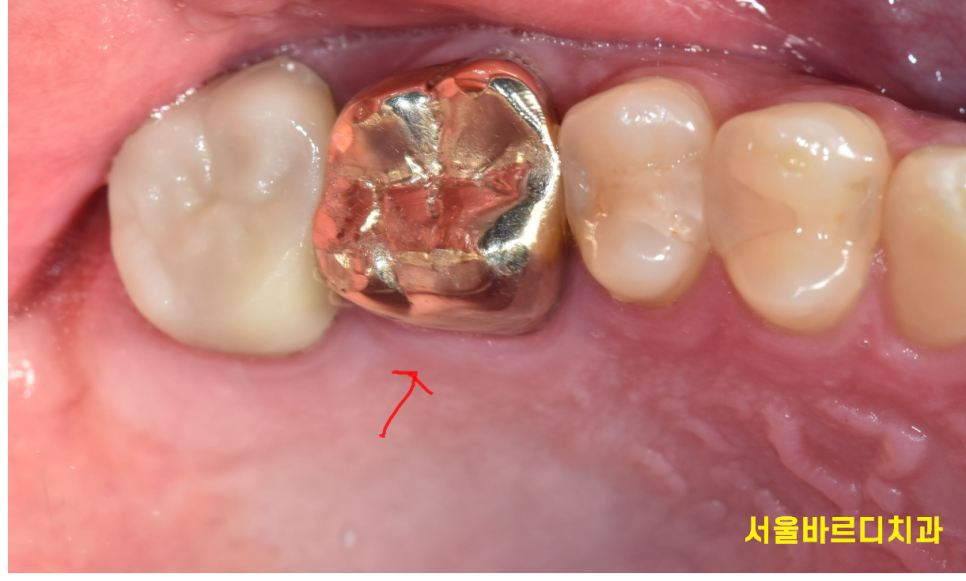

치료를 마친 후 환자분은 더 이상 통증을 느끼지 않으셨고,

문제의 치아는 정상적인 저작 기능을 되찾았습니다.

무엇보다 환자분께서 “자연치아를 유지하게 되어 정말 다행이다”라고 말씀하시며

만족감을 표현해 주셨습니다.